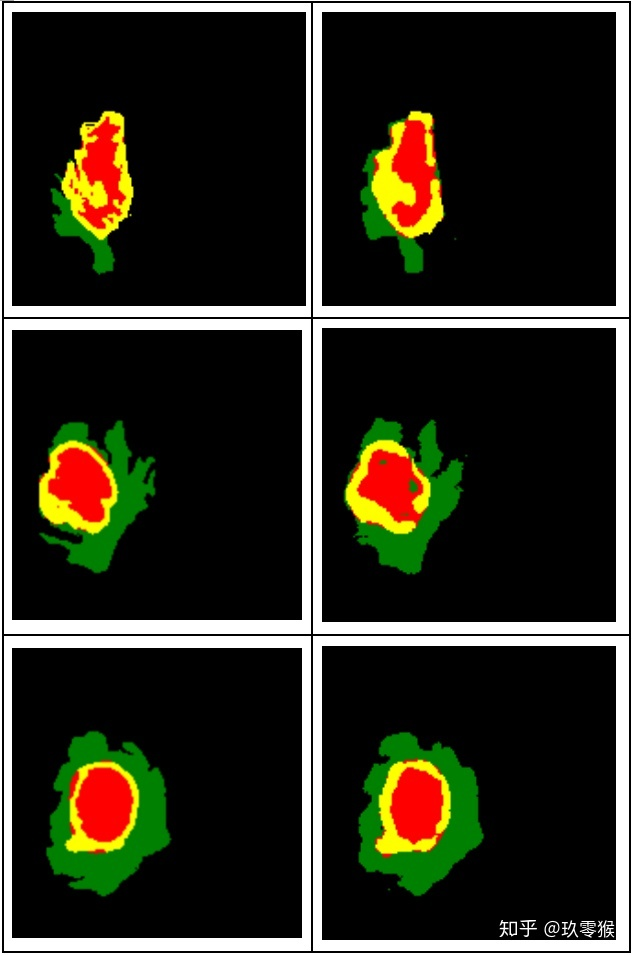

python .\test.py --name="Jiu0Monkey_FCN8s_woDS" --mode="GetPicture"

运行下面指令评价测试结果以及GT文件的指标,想了解更多指标的信息包括Dice、Hausdorff、IOU、PPV等,可以参考我这一篇(分割常用评价指标)

运行的结果: